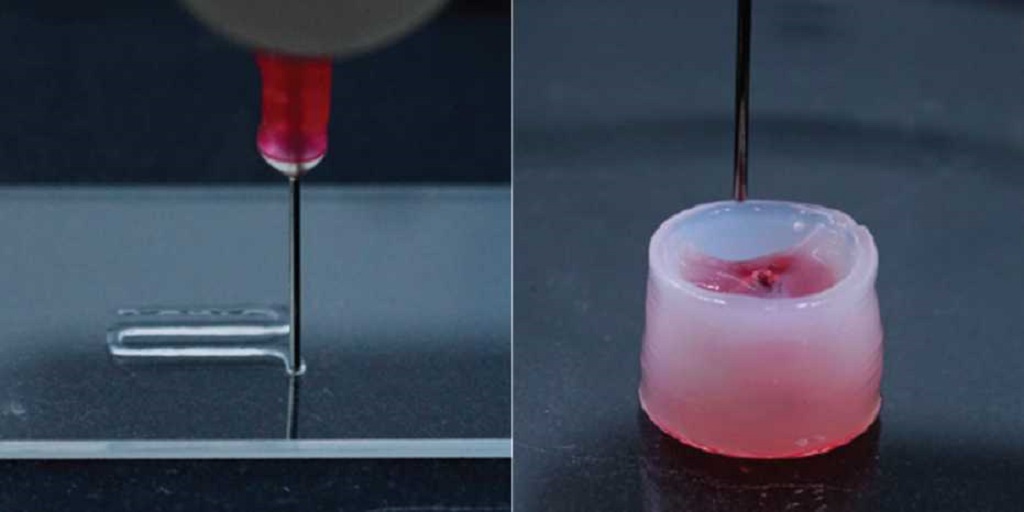

Researchers 3D Print Functional Blood Vessels Using Custom Bioink

Researchers have developed a method of 3D printing blood vessels, and that’s quite important.

New 3D Printed Blood Vessels Could Transform Heart Bypass Operations

Researchers at the University of Edinburgh have developed a method of 3D printing blood vessels.